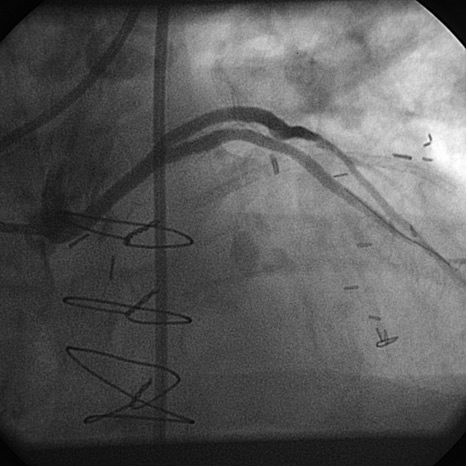

The most commonly used catheters for left heart catheterization and vein graft angiography can be seen in Figure 1 and Figure 4-13. Most of the vein grafts have horizontal take off and can be successfully engaged using a commonly used Judkins right number 4 (JR4) catheter. The JR4 catheter is the most commonly used catheter for the engagement of the right coronary ostium with horizontal take off. However, many vein grafts have unusual take off requiring different catheters. Many right coronary vein grafts have steep inferior take off making the ostial engagement with JR4 difficult or impossible (Figure 10). In such a scenario, a multipurpose catheter which has a shallow angulation is the best choice (Figure 11). The second major challenge in engaging vein graft ostia, particularly vein grafts supplying the left coronary arteries, is the shape of the aorta. A large aorta can make it very difficult for the JR4 catheter to reach the ostial vein grafts. In such a situation, Amplatz (AR) right and left (AL) catheters can be very helpful to reach the vein graft ostia. Amplatz catheters have a larger primary curve and have been used successfully in unusual superior take off of left coronary arteries or vein grafts and in large aorta. Amplatz catheters are available in different sizes (from smaller to larger curve: AR 1, AR2, AL2, AL2 and AL3). Occasionally, a very superior take off of a vein graft requires specially designed bypass graft catheters. Amplatz catheters are also extremely helpful in engaging native right coronary ostium with anterior take off.

PCI of the vein and arterial grafts have unique challenges. For any PCI, guide support is very important for successful balloon and stent delivery. In a tortuous vein graft with a steep angle, advancement of a stent can be very difficult and challenging. Therefore, it is important to choose the best available catheter before starting PCI. Similar to the right coronary angiography, a JR4 guide catheter is most commonly used in this setting. However, Amplatz guide catheters for left vein grafts and multipurpose catheters for right vein grafts are better choices in certain anatomy. In Figure 8 and Figure 10 two examples of poor guide support in two vein graft interventions can be seen. Initially, a JR4 guide was used for PCI of the vein graft supplying the left anterior descending artery (LAD) without any success. However, after changing the guide to an Amplatz left 2 guide catheter, we achieved excellent support without any difficulty in advancing two stents (Figure 9). In Figure 10, difficulty is illustrated in engaging the vein graft ostium supplying the right coronary artery with a JR4 catheter. This vein graft has a very steep inferior take off from the aorta. After changing the guide to a multipurpose catheter, we were able to deliver three stents successfully without any difficulties (Figure 11). Similar challenges exist in the treatment of the left IMA or right IMA. These arterial grafts can be extremely tortuous making stent delivery very difficult. It may be necessary to use short length stents for a better deliverability or stents with lowest profile. Usually, similar to the native coronary intervention, a 6 French guide is appropriate for the routine use.